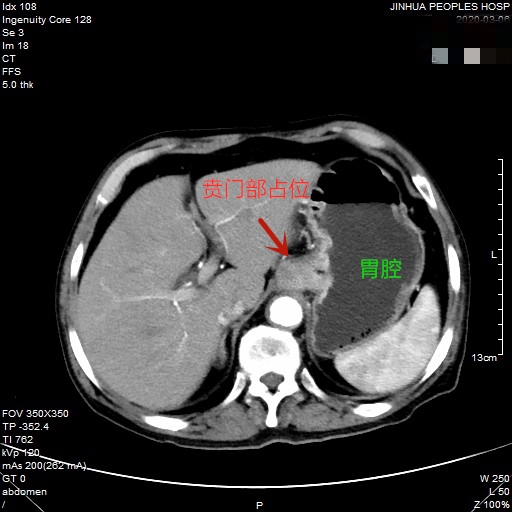

医生予以进一步检查CT增强发现肿瘤倒是没有明显侵犯周围脏器或结构,请我去会诊后,仔细阅片,发现从影像上看还是能够根治性切除的。所以转来胸外科拟进一步行手术治疗。下面是其CT增强的图像:

以上图片红色箭头所指处为贲门部肿瘤